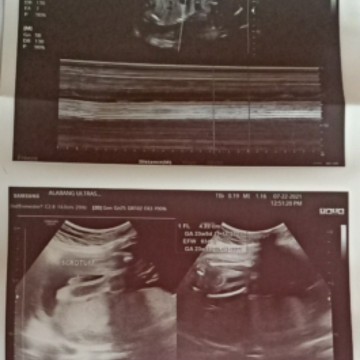

24 weeks utz

Hello mga mommies! Baby boy po kita ang itlog 🥰 pero lahat ng hula ng mga nakakakita saakin ay babae daw kasi palapad ang tyan ko. Saka mahilig ako sa matatamis. 😁 Kaya sobrang saya ko nung sinabi na BOY kasi yun talaga ang dinadasal ko na gender ni baby. 🥰 Hindi naman po ito magkakamali na diba? Mag uunti na kasi kami ng mga gamit ni baby hehe. #1stimemom po. 💖 #24weeks #TeamNovember #firstbaby #pregnancy